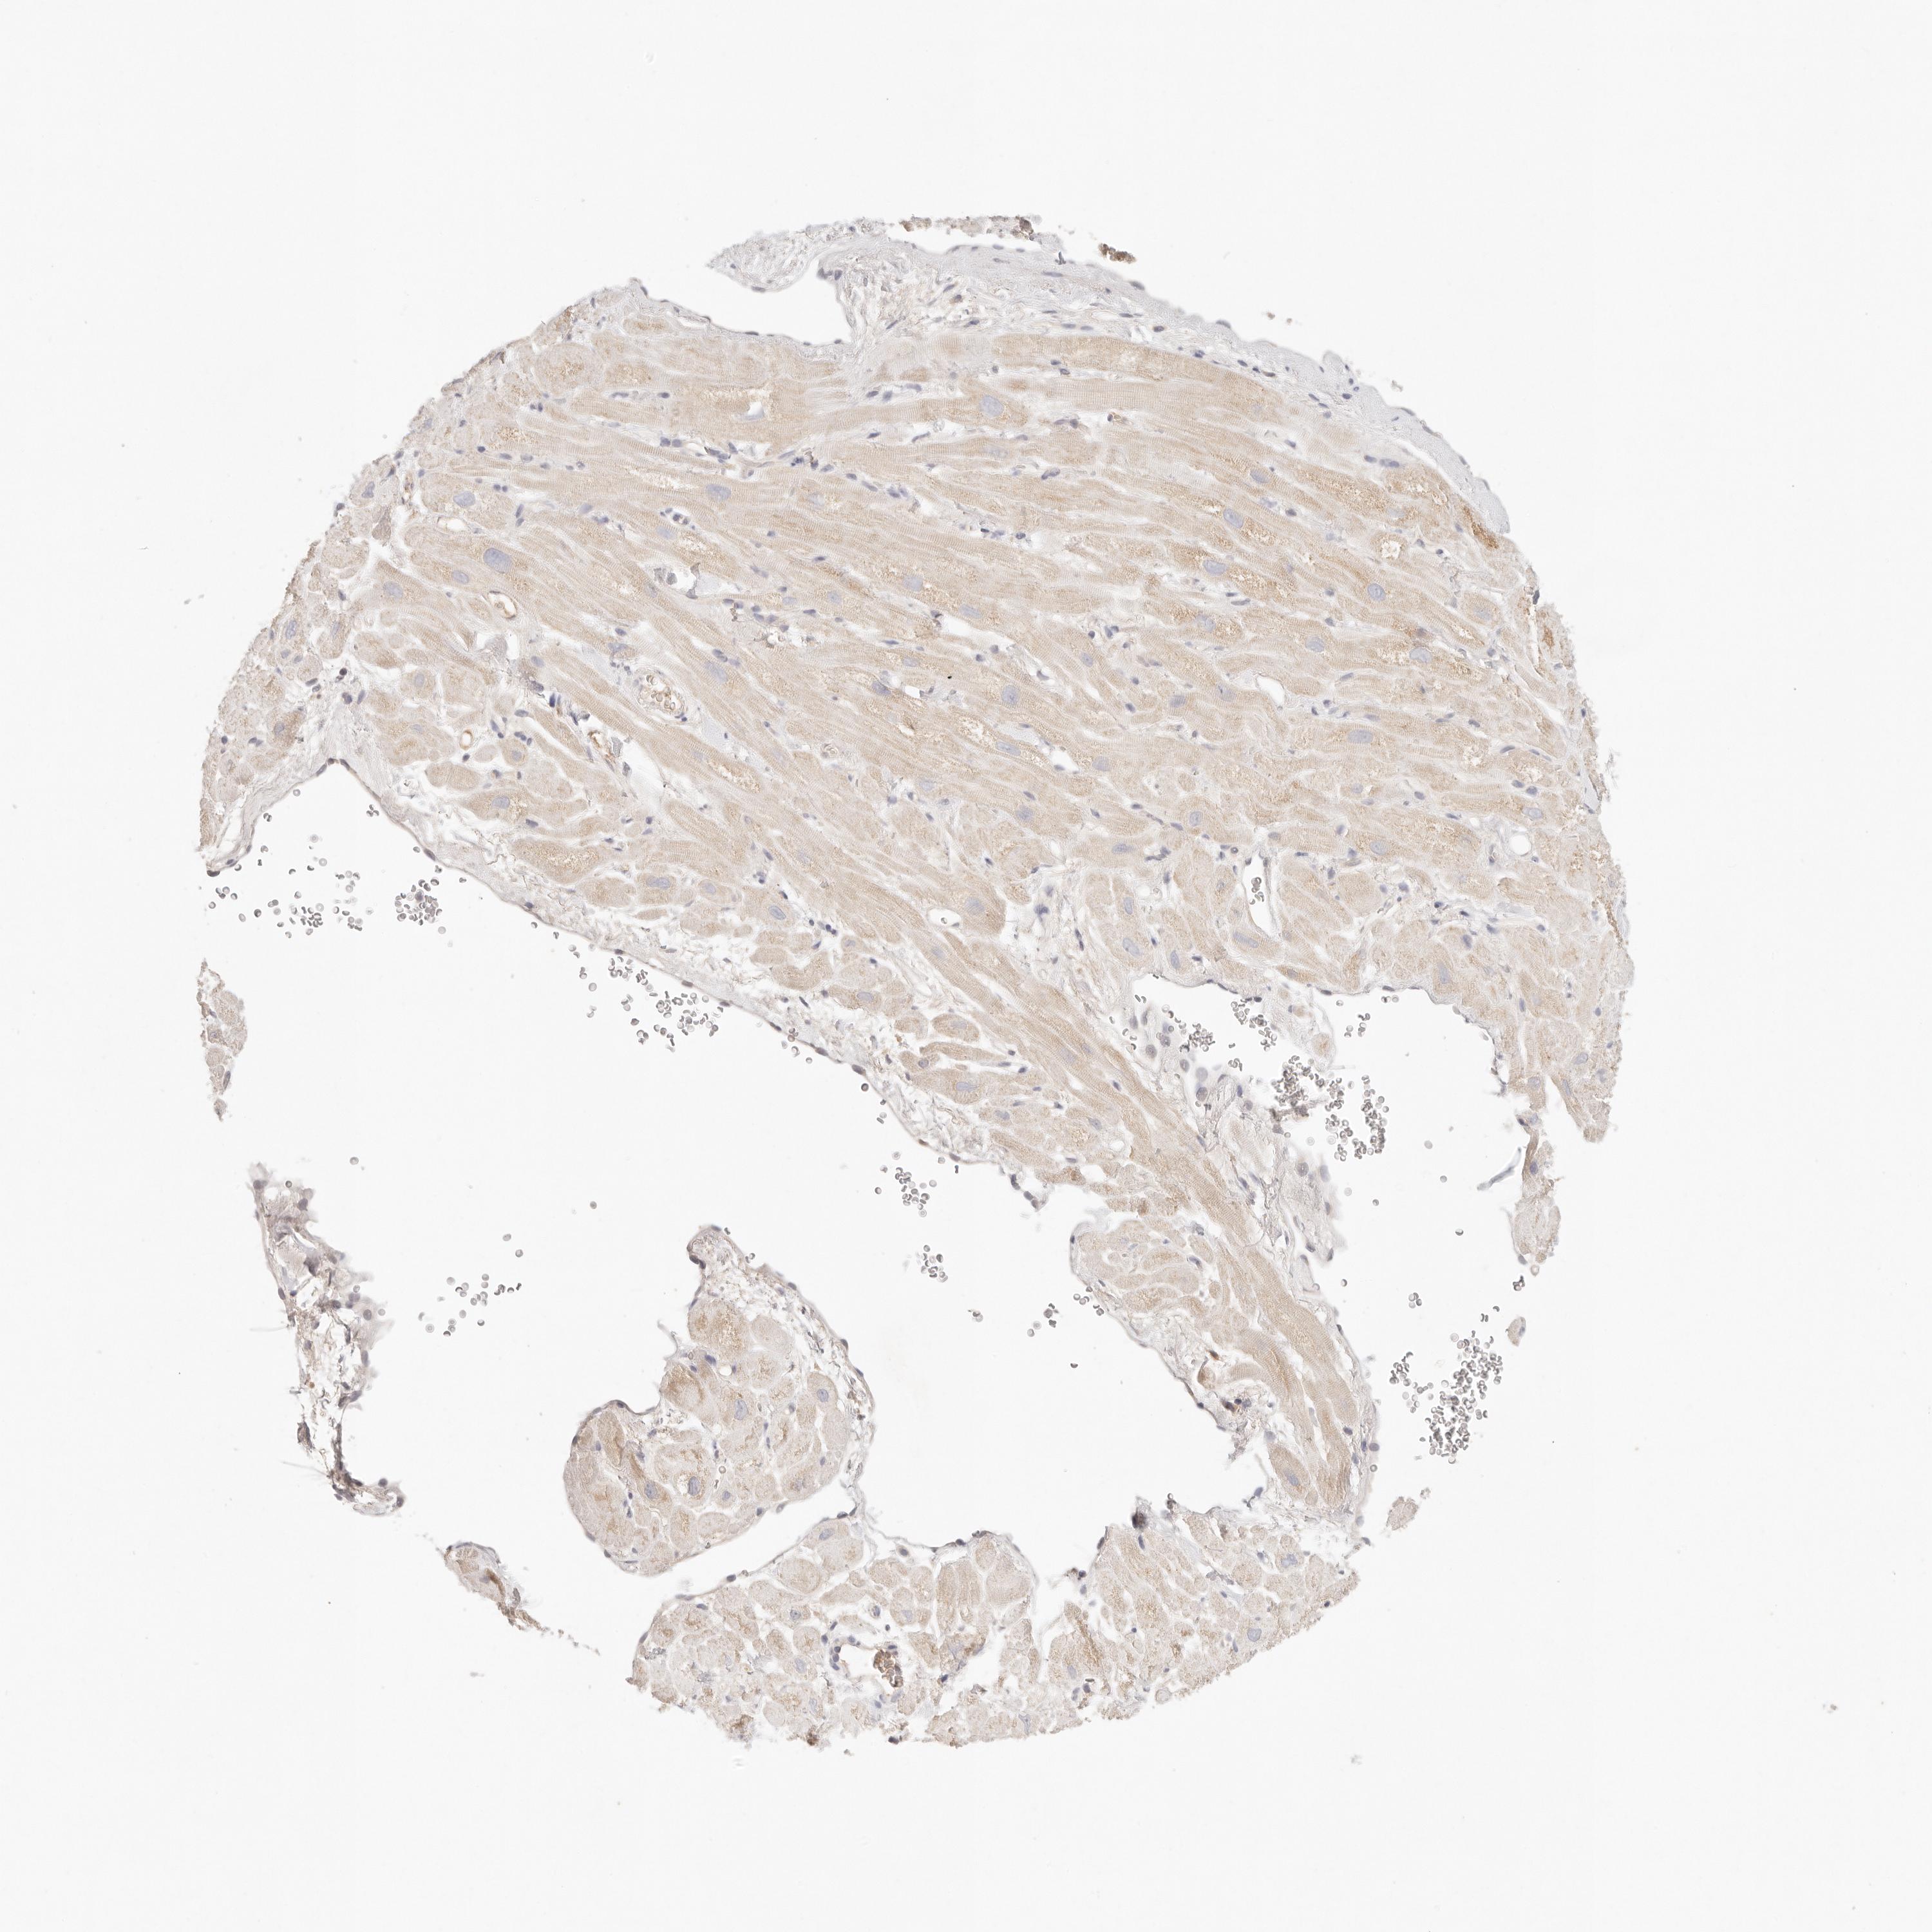

HEART MUSCLE - Antibody stainingi

Antibody staining in the annotated cell types in the current human tissue is reported as not detected, low, medium, or high, based on conventional immunohistochemistry profiling in selected tissues. This score is based on the combination of the staining intensity and fraction of stained cells.

Each image is clickable and will lead to virtual microscopy that enables deeper exploration of all samples and also displays staining intensity scores, fraction scores and subcellular localization as well as patient and tissue information for each sample.

Antibody HPA022829Antibody HPA028761

Cardiomyocytes MediumLow